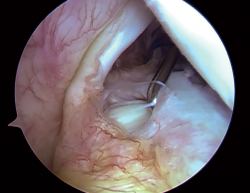

Imagen artroscópica de la cavidad glenohumeral de un hombro derecho desde el portal posterior en una paciente intervenida por luxación recidivante de hombro. En la fotografía puede visualizarse una lesión del complejo bicipitolabral del tipo SLAP 3 según la clasificación de Snyder. Este tipo de lesión se caracteriza por un desgarro en forma de asa de cubo del labrum superior, manteniéndose el tendón de la porción larga del bíceps indemne.